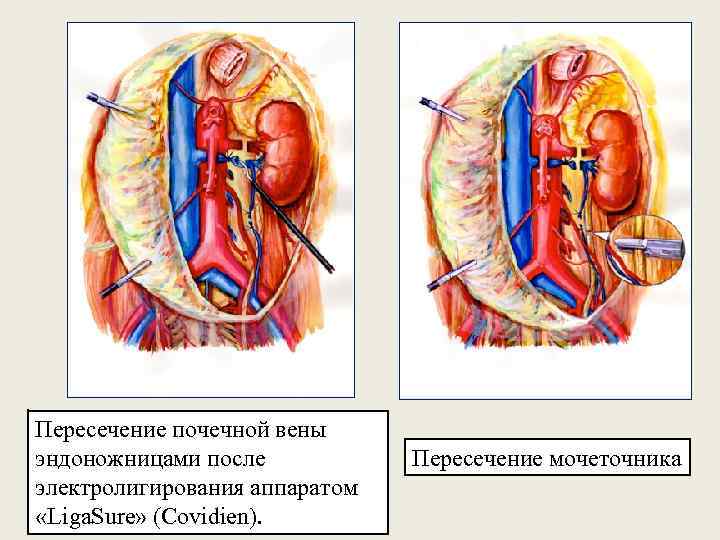

Пересечение почечной вены эндоножницами после электролигирования аппаратом «Liga. Sure» (Covidien). Пересечение мочеточника